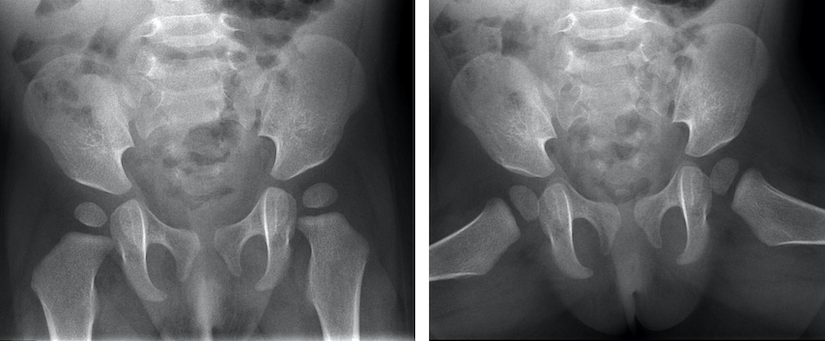

Links: CT-scan van het bekken van een baby van 8 maanden. Dwarsdoorsnede door het heupgewricht. De heupkoppen zijn gemarkeerd met witte pijlen. De linkerheupkop is naar achter (rugzijde) geluxeerd. Dit is op een röntgenfoto niet goed te zien.

Rechts: CT-scan van het bekken van dezelfde baby als figuur 7, 1 maand na repositie. De linkerheupkop staat goed in de kom..

Bij kinderen met heupluxatie kan een CT-scan worden gebruikt om te controleren of de heupkop goed in de heupkom staat als het niet lukt om dit op een andere manier te bekijken.